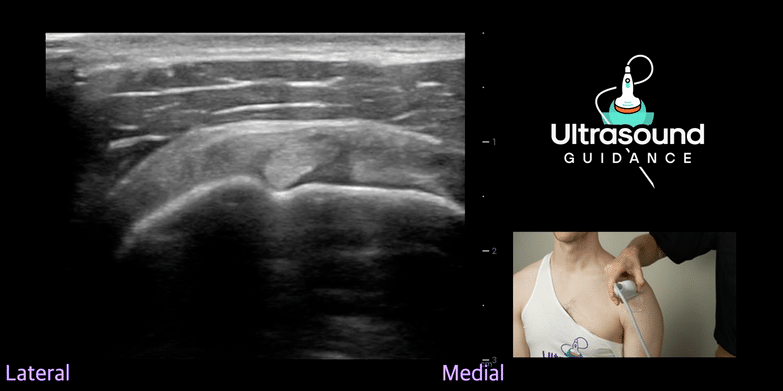

| Common Flexor Tendon Needle Tenotomy | Shoulder | |

| Subacromial/Subdeltoid (SASD) Bursa Injection Sidelying | ||

| Subacromial/Subdeltoid Bursa Injection Supine | ||